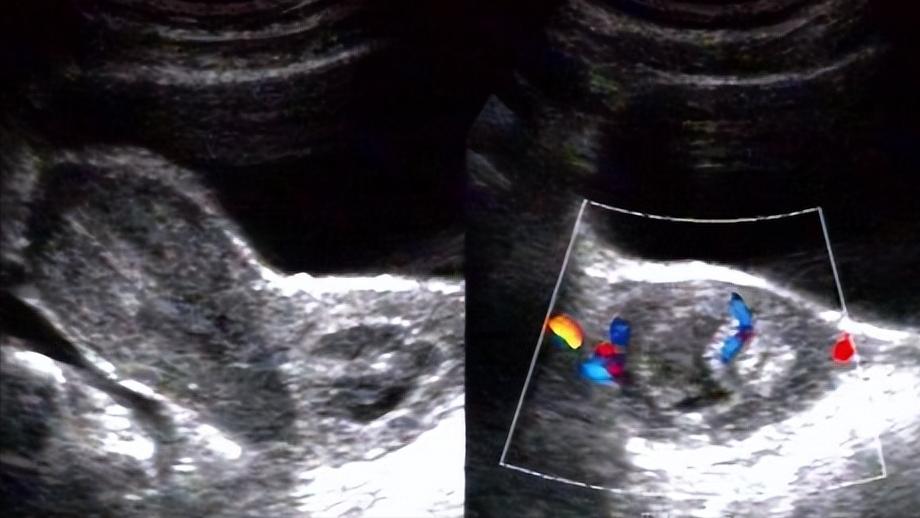

“我当时13岁来的月经,可我女儿今年都16岁了,还没有来,我心里有点膈应,感觉这应该不太正常。这几天,她又和我说肚子疼,搞得我心神不宁的,想来医院看看到底怎么回事。医生,我女儿是生什么病了吗?” 沈女士今年38岁,平时工作挺忙的,对女儿的关心也少了点,尤其是女儿升上高中后,母女俩的交流屈指可数。她想着,女儿这么大了,应该能照顾好自己,不过很显然,沈女士错了。 这几天,沈女士觉得女儿不对劲,老是闷闷不乐的,作业一做完,就躲在屋子里不肯出来。 她赶紧上前询问,女儿却冒出这样一句话:“我们班的女同学几乎都来月经了,只有我一个人没来,根本融不进她们,我也不知道怎么回事。” 原来,女儿真的长大了,沈女士当下才意识到,她安慰完女儿后,和老师请好了假,决定去医院看看。 路上沈女士紧紧抱住女儿,嘴里一直说着没事没事,说实话,她当时也没觉得16岁不来月经是多大的事,毕竟每个人的体质什么的都不一样,晚点来不也很正常吗。可是沈女士并不知道,女儿的身体1年前,就已经不太对劲了。 “我1前就感觉肚子痛痛的,当时身边的人都来姨妈了,我以为自己也要来了,谁知道等了1年也没来,期间还有尿频、胸胀的情况。”女儿到医院后,向医生说道。 天哪,这么大的事,自己居然没有发现,沈女士的心里无比自责。接着医生安排沈女士的女儿做了肛查、妇科检查,其中妇科检查显示:外阴发育正常,可见处女膜完全无空隙,处女膜稍向外膨出,膜后呈紫蓝色。 医生结合各项检查,初步判断是原发性闭经、处女膜闭锁,在经过性激素六项、染色体检查、泌尿系统彩超等检查后,沈女士被告知女儿是处女膜闭锁。 “这是什么意思啊,月经怎么还和处女膜扯上关系了,医生这到底是怎么回事啊?”沈女士实在是急的不行,一把就拉住了医生的胳膊。 处女膜,遮掩在女性阴道外口的一圈薄膜,它有个非常明显的特点,中央有一个直径为1~1.5cm的圆形小孔,我们把它称为处女膜孔。 假如女性的处女膜上没有这个小孔,就可以说是处女膜闭锁。 医生是这样说的:“这一般是处女膜发育旺盛所引起的,当孩子年纪还小时,没有什么症状,可是等青春期月经来潮时,经血就无法排出体外。” 沈女士的女儿之所以会腹痛,也是这个原因,经血被憋在“死胡同”里,会积聚在阴道下段,情况严重时,经血还会通过输卵管伞端倒流到付腹腔,就可能会引起周期性下腹痛,可月经就是不来。 现在该怎么办呢,女儿的年纪还这么小,难不成还要做手术吗,沈女士感到一丝恐惧,可医生的话给她泼了一盆冷水。 “这个是需要做手术,如果没有及时发现、治疗,经血会在阴道内的积聚,经年累月后可能会向上扩展到输卵管和子宫腔,最终甚至会导致盆腔炎、子宫内膜异位症,影响生育。“医生解释道。 沈女士听完心里不是滋味,她摸了摸女儿的头,和医生说愿意接受治疗。入院后经过处女膜“+”型切开引流,引流出陈旧性积血500ml,手术可算是顺利结束了。 术后,沈女士女儿的腹痛症状有明显缓解,后经过身体检查后,便在医生的允许下出院了。医生看到孩子的心情,不再像看病时那么沉闷,恢复了这个年龄段该有的快乐。 @妇产科主任赵先兰帮您科普[送心] [what]沈女士的故事,告诉了我们什么? 女孩处于青春期,家长一定要留心孩子的变化,有些孩子感觉不对劲,但会由于害羞不好意思说出口,可能会一拖再拖,耽误后续的治疗。 一般来说,女孩的初潮在13~14,不过早的可能会在11岁,晚的要16岁,如果孩子16岁后还没有来月经,建议家长带着来医院做做检查,不要忽视。不过大家不用过于担心,处女膜闭锁及时治疗,是不会影响生育的。 #头条创作挑战赛#